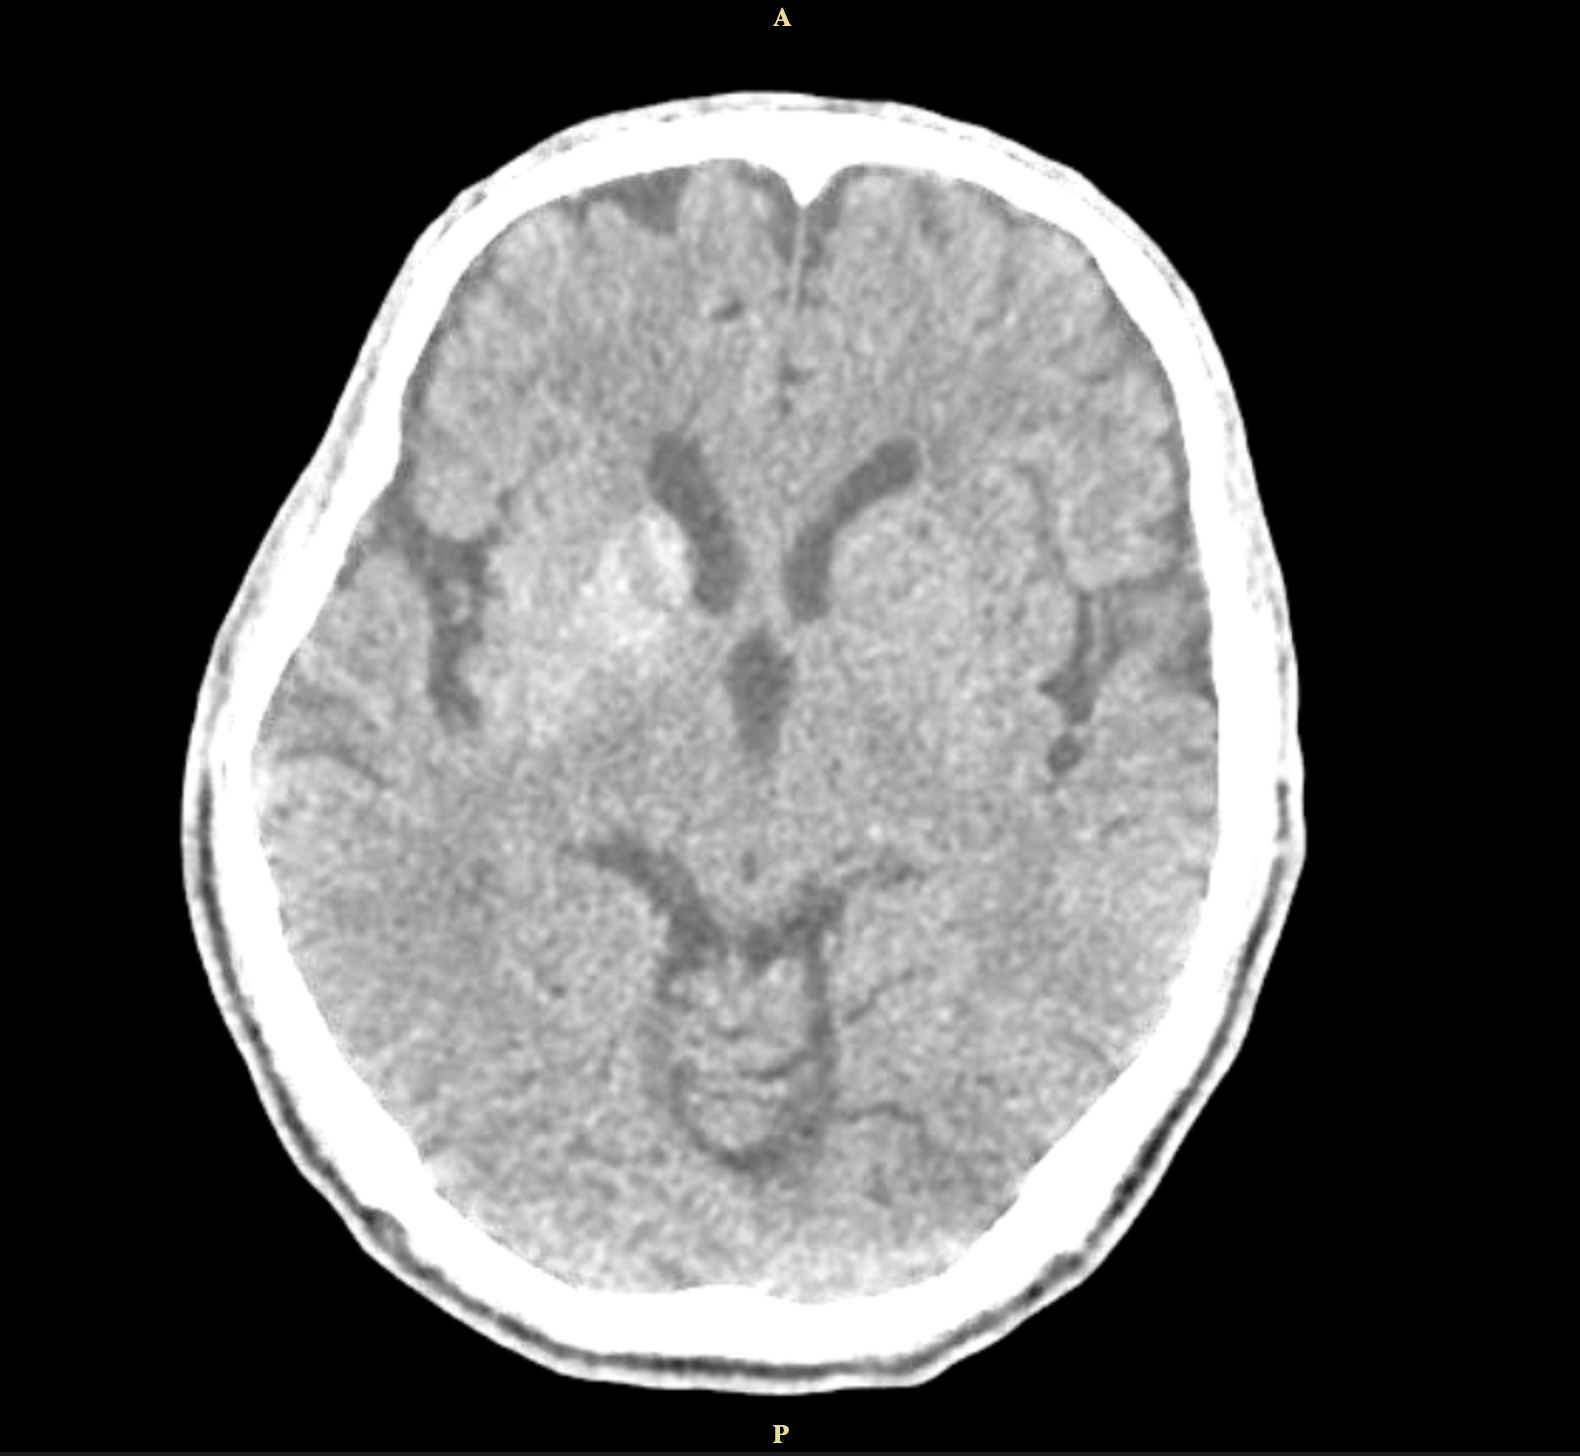

Method: A 62-year-old man with uncontrolled diabetes presented with left-sided involuntary movements and slurred speech. His blood glucose was elevated at 576mg/dl, and CT imaging showed hyperdensity in the right caudate and lentiform nuclei. His condition improved with glycemic control, and antichoreic medications were not needed.

Results: This condition occurs in about 1 in 100,000 individuals. Diagnosis relies on neuroimaging, particularly CT or MRI, which reveal basal ganglia lesions, often in the putamen or caudate nucleus. The hallmark finding is striatal hyperintensity without mass effect, sparing the internal capsule. CT has a sensitivity of 78%, and MRI 95% for detecting diabetic striatopathy, with resolution times ranging from 10 to 60 days.

Conclusion: The classic triad for diabetic striatopathy includes poor glycemic control, unilateral striatal hyperdensity on CT imaging, and contralateral choreic movements. Treatment involves achieving euglycemia and managing chorea. Symptom resolution can occur within 2–14 days, with glycemic control alone resolving symptoms in 25% of cases. Adding anti-choreic medications increases resolution to 76%. He continued intensive insulin therapy for 6 months, leading to improvement and eventual resolution of left-sided movement.

Figure 1.2